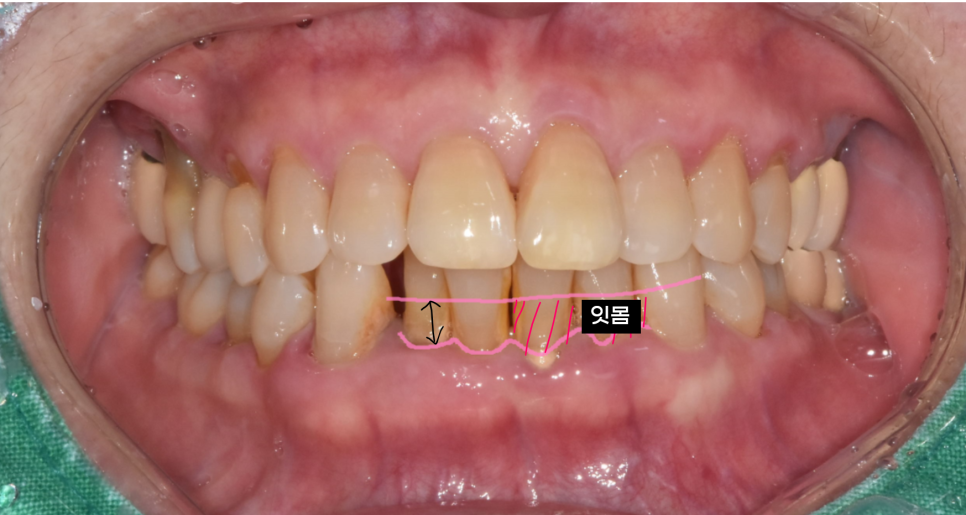

치아가 점점 더 길어지는 이유

사진을 보시면 아래 앞니 1개가 솟구쳐 올라와있죠?

다른 치아에 비해 키가 유독 큰 모습입니다.

“요즘 자꾸 윗니랑 부딪혀서 불편해요”,

“치아를 조금만 깎아주세요” 하고 오시는 경우가 많습니다.

하지만 이건 치아가 자라는 게 아닙니다.

잇몸이 내려가면서 뿌리 부분까지 노출되어 길어져 보이는 것일뿐

실제 치아 길이가 길어진 것은 아닌데요.

뿌리 일부가 노출되며 치아가 길어진 것처럼 보이고,

결국에는 제자리를 이탈해 위로 솟구쳐 오릅니다.

240517 잇몸이 덮여져 있어야할 부분이 내려가기에 치아가 길어져 보이는 현상이 생겨요

그 상태에서 맞물림이 어긋나고,

씹을 때 불편감을 느끼게 되는 거죠.